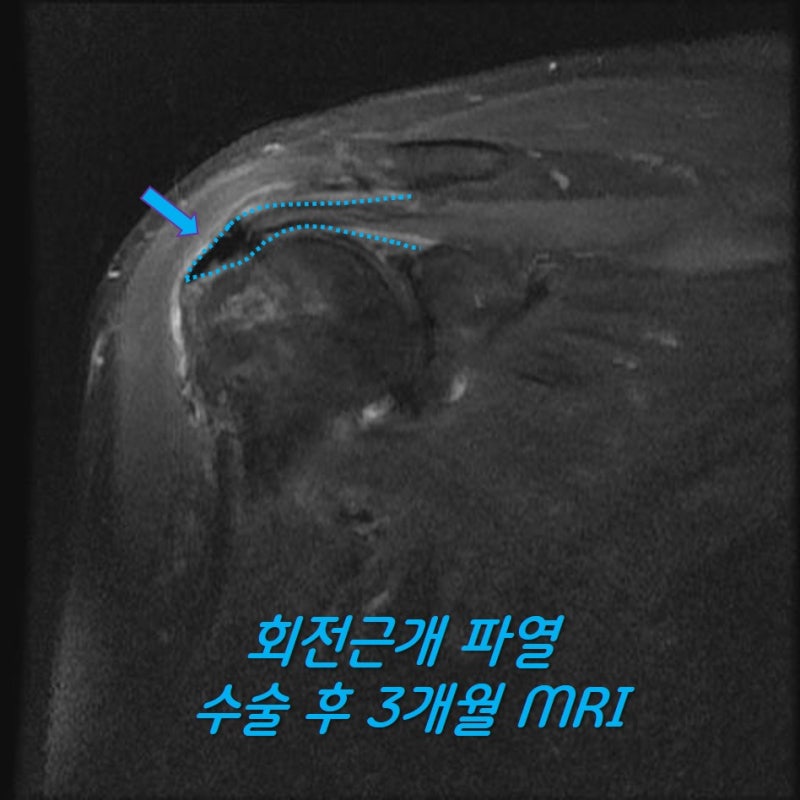

수술 후 3개월차에 다시 MRI 영상을 확인해 보았습니다.

광범위한 회전근개 파열이 있는 경우 완전히 해부학적으로 복원되지 않는 경우가 있습니다. 할 수 있는 만큼만 봉합을 한 경우 회전근개의 부착 부위가 원래의 해부학적으로 부착하는 것보다 적어지기 때문에 재파열이 발생할 가능성이 있고 회전근개의 기능의 회복도 잘 되지 않을 가능성이 많습니다. 이러한 경우 인조인대를 이용하여 보강술을 해주면 원래의 모양대로 해부학적인 복원이 가능하게 됩니다. 인조인대를 이용한 보강술을 술기가 복잡하고 어렵게 때문에 이러한 수술을 하는 병원이 많지는 않습니다. 모든 수술의 원칙은 손상된 조직의 해부학적인 복원입니다. 이를 할 수 없는 경우라도 최대한 근접하게 복원하는 것이 좋은 결과를 위해 매우 중요하다고 생각합니다. 환자분은 현재는 거의 정상적으로 활동하고 계시며 매우 만족하며 생활하신다고 합니다. 해부학적으로 복원 불가한 광범위 회전근개파열도 정상으로 회복될 수 있습니다!!!